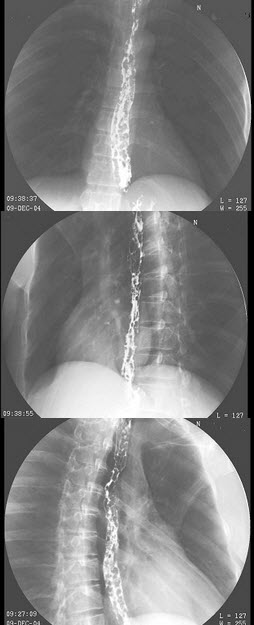

26、单项选择题

女,12岁,脊柱侧弯畸形,双下肢长短不一,结合图像,最可能的诊断是()

A.骨纤维结构不良

B.骨巨细胞瘤

C.内生软骨瘤

D.非骨化性纤维瘤

E.Paget病